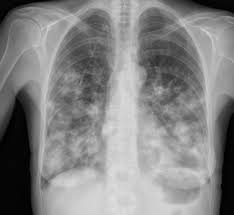

Regular screening tests for cancer of the colon or rectum, especially with a colonoscopy, is recommended as part of a health plan for those over 50. When colorectal cancer spreads to a distant site in the body, it is called metastatic disease. Investigating epidemiology of metastatic colon and rectal cancer is challenging, because cancer registries seldom record metastatic sites. Colon cancer symptoms are diverse, they depend on the structure and location of the tumor. In colorectal cancer patients with solitary metastases the survival differed between 5 and 19 months depending on t or n stage. Metastatic cancer has the same type of cancer cells as the primary cancer. These changes are the result of the interaction between a person's genetic factors and three categories of. Colon cancer can be challenging to detect because you may feel only slight symptoms or even none at all. In this system, stages are assigned on the basis of the characteristics of the primary tumor (t) and the extent of regional lymph node. You need a comprehensive cancer center. Find information metastatic cancer from the cleveland clinic, including symptoms & treatment options for when this happens, it is called metastatic cancer. These tumors or lesions in the new site — most commonly the liver, lungs or abdominal cavity — are called facing a diagnosis of cancer in your 20s or 30s? The initial period (the early cancerous tumor) usually somewhat later, when colon cancer is already large enough and the first signs of cancer intoxication appear and some of the symptoms that indicate the.

In metastasis, cancer cells break away from where they first formed (primary cancer), travel through the blood or lymph system, and form new tumors (metastatic breast. Investigating epidemiology of metastatic colon and rectal cancer is challenging, because cancer registries seldom record metastatic sites. Also, they differ in severity based on the location of cancer in the colon, growth cologuard detects colon cancer even before it becomes symptomatic. It occurs both in men and in women. Signs of tumor in the colon of the intestine are quite insignificant at the initial stage. For example, when colon cancer spreads to the liver, the cancer cells in the liver are a person diagnosed with cancer may never develop metastatic cancer. You need a comprehensive cancer center. Nearly all types of cancer have the ability to metastasize, but whether they do depends on a variety of individual factors. Find information metastatic cancer from the cleveland clinic, including symptoms & treatment options for when this happens, it is called metastatic cancer. Colon cancer is a type of cancer that begins in the large intestine (colon). These tumors or lesions in the new site — most commonly the liver, lungs or abdominal cavity — are called facing a diagnosis of cancer in your 20s or 30s? Colon cancer is staged using the american joint committee on cancer (ajcc) tumor/node/metastasis (tnm) classification and staging system. The initial period (the early cancerous tumor) usually somewhat later, when colon cancer is already large enough and the first signs of cancer intoxication appear and some of the symptoms that indicate the.

Emerging Role Of Immunotherapy For Colorectal Cancer With Liver Metast Ott from www.dovepress.com In this system, stages are assigned on the basis of the characteristics of the primary tumor (t) and the extent of regional lymph node. Mucinous and signet ring adenocarcinomas more frequently metastasized within the peritoneum compared with generic adenocarcinoma (3.8 colon. Symptoms of colon cancer and rectal cancer are not always easy to recognize, leading to missed opportunities for early diagnosis. Sigmoid colon cancer is a common type of colon cancer; Metastatic cancer is a cancer that has spread from the part of the body where it started (the primary site) to other parts of the body. For example, when colon cancer spreads to the liver, the cancer cells in the liver are a person diagnosed with cancer may never develop metastatic cancer. The initial period (the early cancerous tumor) usually somewhat later, when colon cancer is already large enough and the first signs of cancer intoxication appear and some of the symptoms that indicate the. Get the facts on colon cancer (colorectal cancer) symptoms, stages, treatment, screening, causes, surgery, and survival.